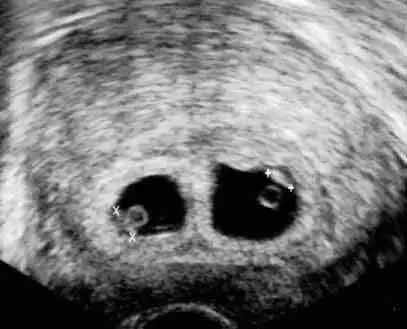

Masallah kuzum gözün AydınRandevudan çıktım ama nasıl sevineyim bilmiyorumkarından ultrasonda gözükmedi zibidi. Transvajinal ultrasonda gözüktü. Sorun şu ki kesenin ortasından ayıran bi bölme var, ya ikiz gebelik ya da sebebini bilmediğim başka bişey. Doktorum da bilmiyor sanırım başka bi doktor arkadaşına danışacakmış. Kan da verdim saat 2 de anlayacağız bakalım neymiş. Doktor bir sorun yok dedi, haftalar da uyuşuyormuş, minicikmiş daha

ultrason görüntüsünden anlayan varsa seslensin de atayım görüntüyü

Allah allah yoksa ikiz miRandevudan çıktım ama nasıl sevineyim bilmiyorumkarından ultrasonda gözükmedi zibidi. Transvajinal ultrasonda gözüktü. Sorun şu ki kesenin ortasından ayıran bi bölme var, ya ikiz gebelik ya da sebebini bilmediğim başka bişey. Doktorum da bilmiyor sanırım başka bi doktor arkadaşına danışacakmış. Kan da verdim saat 2 de anlayacağız bakalım neymiş. Doktor bir sorun yok dedi, haftalar da uyuşuyormuş, minicikmiş daha

İşin ilginç yanı ikiz beklemiyorduk hiç yani ben pek ihtimal vermiyordumMasallah kuzum gözün Aydınikiz gebelik olabilir bak ortadan bi ayrım varsa

Zor olur ama çok güzel de olurAy ay ay ne güzel olur ya ikiz olursaat resmi belki anlayan olur kuşum

Valla google a ikiz gebelik 5 hafta yazdım çıkan sonuç buZor olur ama çok güzel de olurYükledim bakalım bilen varsa yazar inşallah